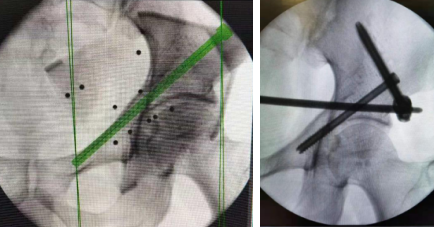

6月3日,手术团队为患者进行了“骨盆骨折天玑机器人导航下复位内固定术”。术中,在天玑骨科机器人导航下精准定位,使用infix内固定固定。仅用一个多小时,手术顺利完成。

机器人导航下置入螺钉

手术切口2公分